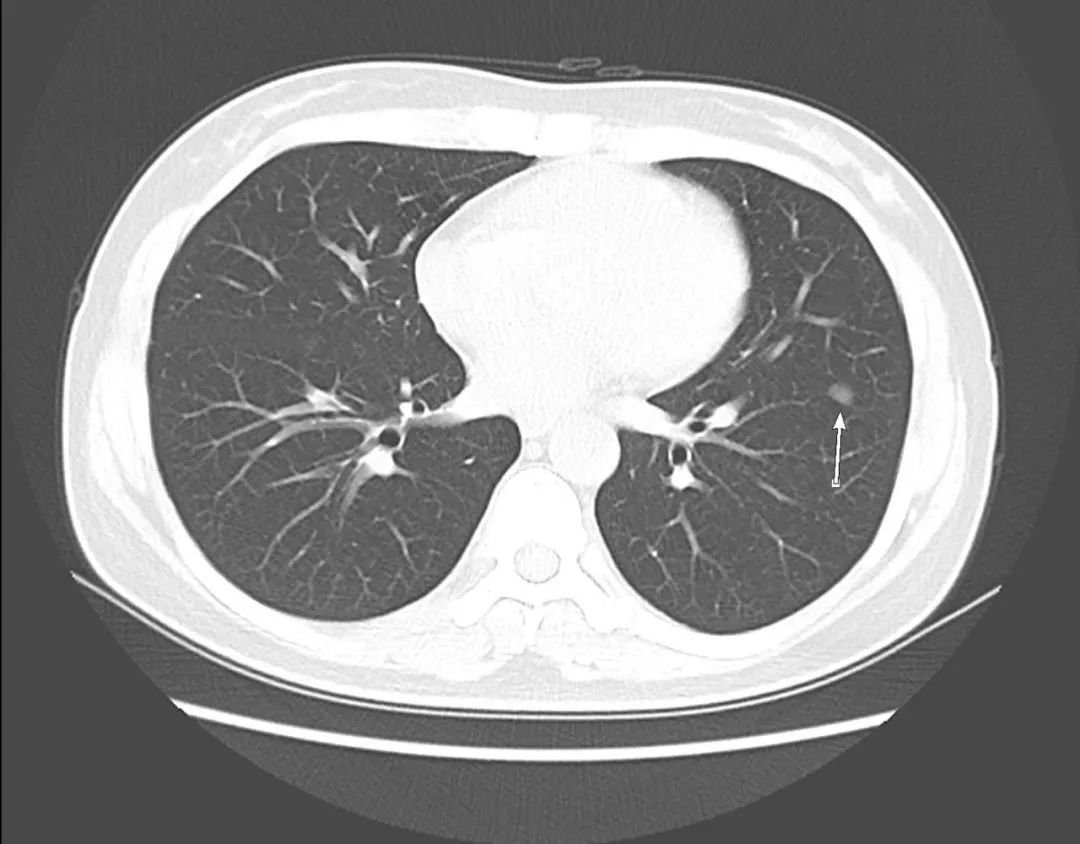

在报告单上查迅速查到患者ID,是胸部CT平扫(含上腹)检查,打开了图像,大致浏览了全层图像,找到了报告标注的左肺结节。一眼看上去,觉得是一个光滑结节,不像是腺癌一样恶性磨玻璃结节。患者只做了肺部CT平扫,肺窗只有5mm,只能在两个层面观察到结节,提供的信息很少。

等等,我看到了最后面0.625mm序列的纵隔窗,我调成肺窗,和5mm厚层对准,终于找到了所谓磨玻璃结节的层面,原来是左肺叶间裂胸膜结节样增厚,在厚层上呈现结节。

这不是第一次将胸膜当成肺内结节,如果稍加注意,调一下窗宽窗位,可能就能避免使患者一家人惶惶不可终日,让他们多一些心安。

纵隔窗调成肺窗,显示左肺叶间裂结节样增厚